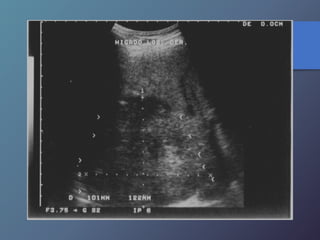

Traumatismo Hepático

• La lesión hepática es a predominio del lóbulo derecho.

• Mayor particularidad en segmento posterior.

• Mayor frecuencia por laceración peri vascular.

• Se producen hematomas subcapsulares,

pericapsulares o aislados.

• La hemorragia en las primeras 24 horas es ecogénica y

posteriormente se hace mas hipoecogénica.

• Entre las dos o tres semanas se puede observar gran

cantidad tejido de granulación.